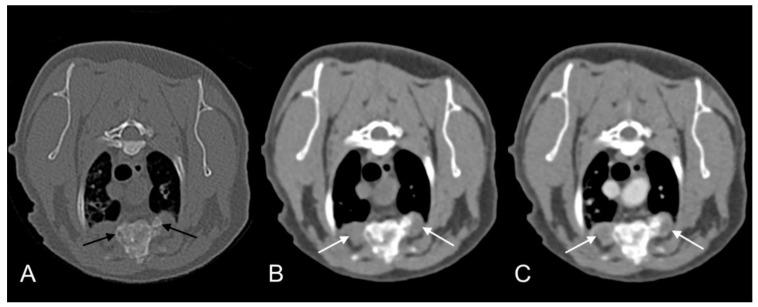

分枝杆菌感染是兽医学中的一个主要问题,因为病因诊断困难、治疗面临挑战且存在人畜共患病风险。,一种生长缓慢的非结核分枝杆菌,可导致人类和动物患病。虽然人类感染已有详细描述,可能被误诊为结核病,但动物感染的报道较少。家猫中仅报道过4例。本病例报告描述了两只同窝的室内猫的全身感染,它们分别在两年半的时间里出现皮肤疾病,并伴有溶骨性和肺部病变。通过对一只猫腰骶部软组织肿块的细针穿刺抽吸物以及另一只猫皮肤病变的组织块活检进行聚合酶链反应,证实两只猫均感染了。干扰素-γ释放试验分别推断两只猫感染了-复合体和-复合体。两只猫在接受利福平、阿奇霉素和普拉德氟沙星抗菌治疗(猫2加用N-乙酰半胱氨酸)后均完全康复。本报告强调了猫全身分枝杆菌病的成功治疗以及准确诊断这种感染的挑战。

Use of computed tomography imaging during long-term follow-up of nine feline tuberculosis cases.九例猫结核病病例长期随访期间计算机断层扫描成像的应用